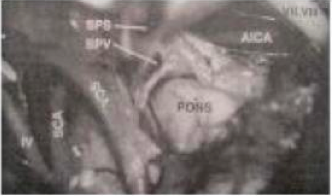

Pendekatan apa yang paling memungkinakan untuk digunakan dalam rangka memperileh paparan bedah ini

A. Trans-Sylvian pterional

B. Subtemporal

C. Suboksipital Garis tengah

D. Fossa Infra temporal

E. Transpetrous Prasigmoid

E